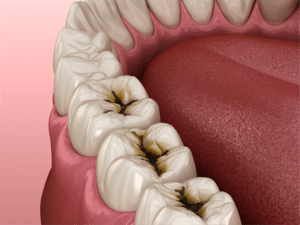

虫歯の進行と進行速度

虫歯の前兆から最重度の虫歯までの流れのイメージ図

虫歯の進行速度はお口の中の環境によってかなり変わってきます。

歯の状態、はえ方、唾液の量、飲食物、歯ブラシのタイミングがその最たるものです。

上の図のように歯は上から進行するとは限らず、歯の側面からも進行し得ます。

乳歯や永久歯でもはえたては虫歯の進行は速いです。

唾液の量が少ないと虫歯になりやすいですし、進行も速いです。

砂糖や酸性のものの飲食が好きな方は進行が速いです。

歯を磨くタイミングがない、少ない方も虫歯になりやすいです。